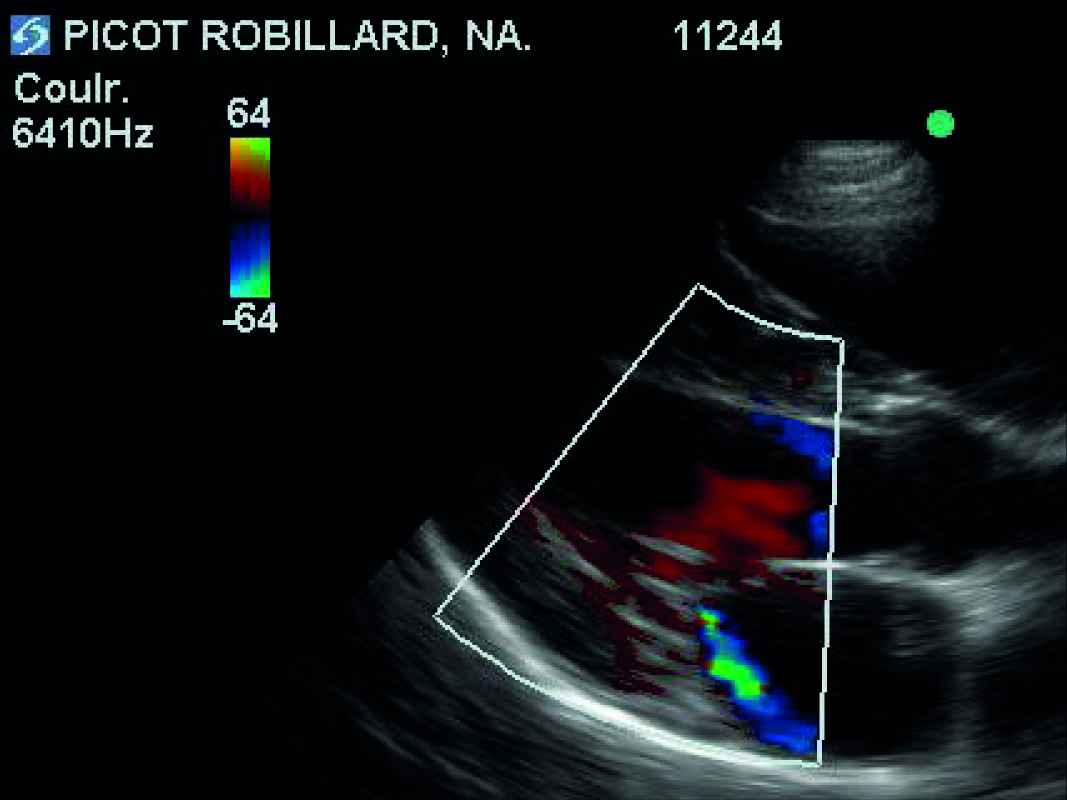

- L'examen échocardiographique révèle une insuffisance de la valve mitrale centrale, peu évoluée, sans aucun remodelage des feuillets mitraux, ni modifications des dimensions de l'atrium gauche et du ventricule gauche (VG normalisé à 1,7 : discrètement au-dessus de la norme) : stade ACVIM B1. La distance point E-Septum est estimée à 10 mm (norme supérieure acceptée : 7 mm). On note donc essentiellement une mauvaise fermeture des feuillets mitraux par agrandissement de l'anneau mitral. Enfin, une petite fuite pulmonaire est visualisée mais sans aucune répercussion sur l'état clinique ou hémodynamique du coeur (cavités droites sans aucun signe de souffrance).

Un suivi clinique et échocardiographique (tableau n° 2, photos n° 1, 2 et 3), électrocardiographique (photo n° 4) et mesure du NT-proBNP (tableau n° 3) sont entrepris sur 12 mois avec une visite à 4 mois (V2), 6 mois (V3) et 12 mois (V4).

Au cours des examens échocardiographiques, une très faible dilatation de l'atrium gauche a été observée (passage d'un rapport OG/Ao de 1 à 1,4). La dilatation du VG ne s'est pas aggravée au cours des 12 mois (42 mm en télédiastole à V1 et V4). On note une amélioration puis une stabilisation de la distance point E-Septum.